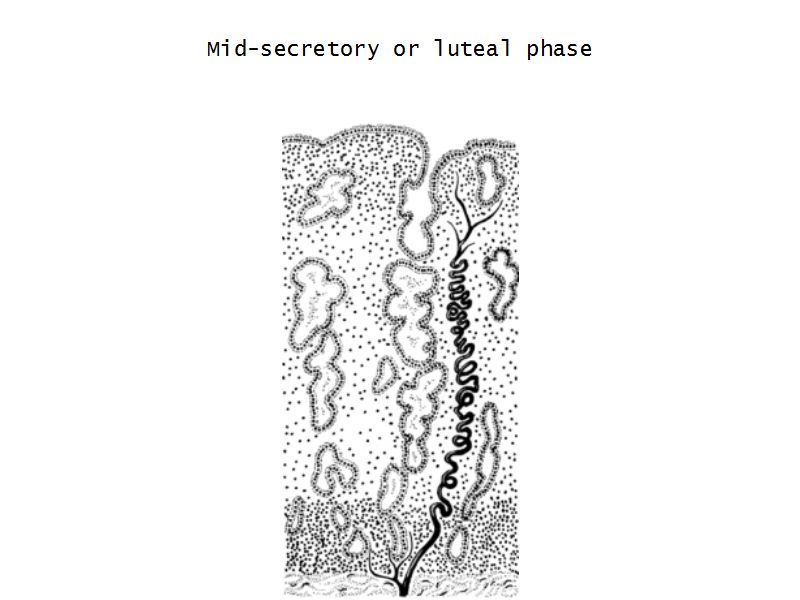

Menstrual cycle

- Luteal phase

Luteal phase

- Thickening endometrium

- Edema

- Endometrial gland secretion

- Glands

- Glandular cells at apex

- Basal accumulation glycogen

- Helical arteries reach superficial regions